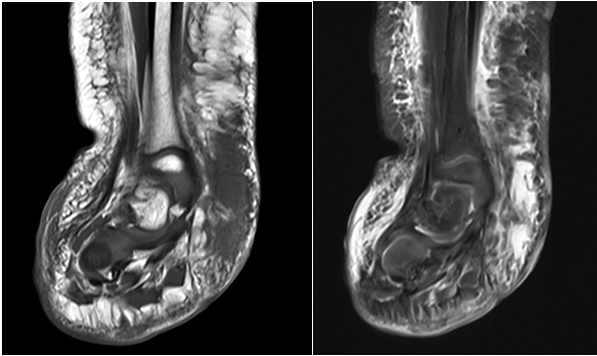

A 4-year-old boy presented to the clinic 2 years ago with well-defined, hyperkeratotic, erythematous plaques in a linear pattern over the medial aspect of his right tibia, extending to his ankle. These lesions were present at birth as flat, pink macules that were initially identified as a port wine stain (Figure 1). The initial treatment was with a pulsed dye laser (595-nm wavelength), but it did not respond. The macules grew hyperkeratotic and verrucous over time (Figure 2). Oral propranolol (20 mg bid) was initiated to no avail. Sonographic assessment of the medial aspect of the right ankle showed a widening of the subcutaneous space with amorphous, hyperechoic lesions without any significant internal flow (Figure 3). Further contrast-enhanced computed tomography shows skin thickening and soft tissue density at the medial aspect of the right ankle in the dermal and subcutaneous space (Figure 4). Additional magnetic resonance imaging (MRI) from March 2020 to evaluate superimposed cellulitis showed a 3.5 × 1.1 × 4.3-cm T1 intermediate, T2 hyperintense mass confined to the subcutaneous soft tissue along the medial aspect of the ankle along with extensive subcutaneous edema (Figure 5). The lesions were biopsied and positive for GLUT1 and a diagnosis of VVM was made. During his results at 1 year, a surgical approach was chosen. However, due to the location in the distal third of the lower leg involving the ankle, complete extirpation was not possible without necessitating a complex reconstruction (Figure 6). The lesions were partially excised to a depth of normal-appearing subcutaneous tissue. The resultant wounds were closed primarily. Our patient recovered well and healed without complications.

Figure 5. Coronal magnetic resonance imaging demonstrates a T1 intermediate T2 hyperintense lesion in the subcutaneous space.